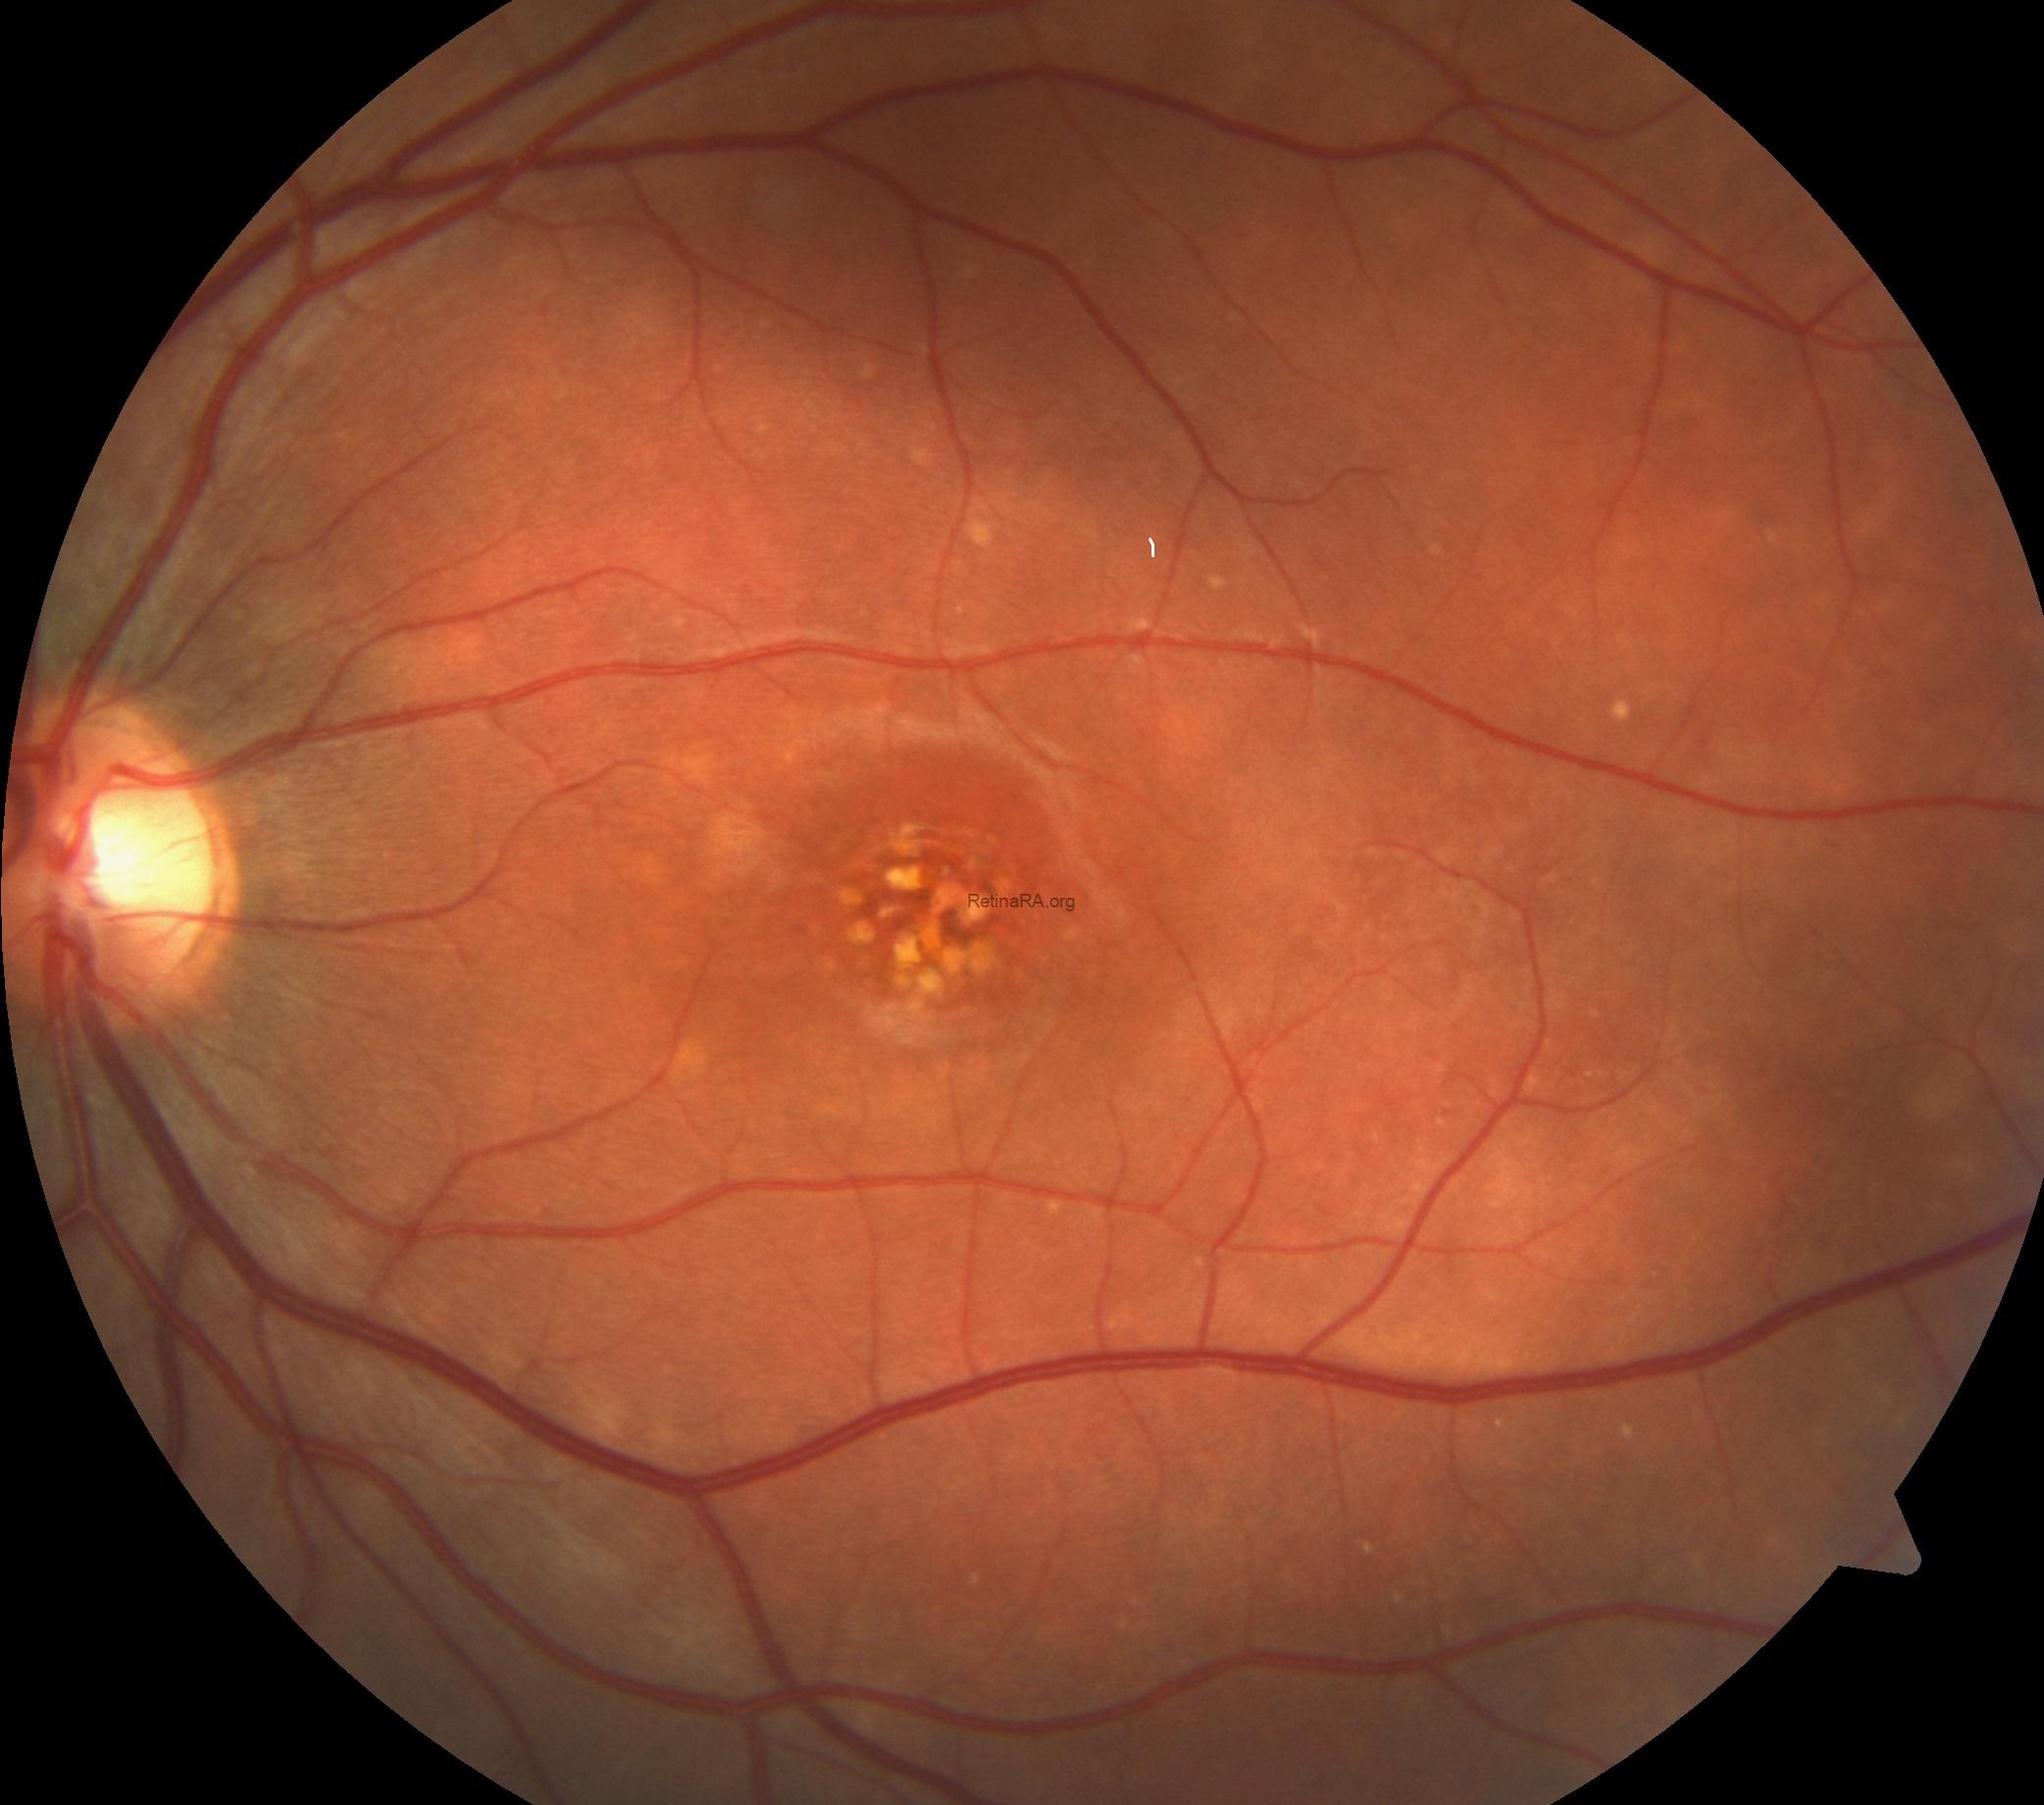

Dilated fundus examination showed bilateral maculopathy with multifocal subretinal white-yellow deposits in the macula and posterior pole of both eyes.